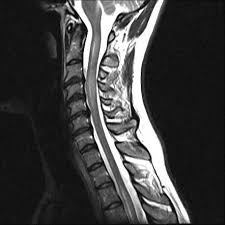

Abb 1 8 A Langstreckige Zervikale Myelitis Von Hohe Der Download Scientific Diagram from www.researchgate.net Klinische eigenschaften von tm transverse myelitis (tm) ist ein akuter entzündlicher prozess, der einen fokalen herd im rückenmark betrifft. Acute transverse myelitis is acute inflammation of gray and white matter in one or more adjacent spinal cord segments, usually thoracic. Transverse myelitis association nonprofit organization dedicated to advocacy for those who have rare neuroimmunologic diseases of the central nervous system, including transverse myelitis (tm), acute. Transverse myelitis (in latin nomenclature: Acute transverse myelitis (atm) is an inflammatory condition affecting both halves of the spinal cord and associated with rapidly progressive motor, sensory, and autonomic dysfunction. Tm may be due to a virus or other infection, but in general, the cause is unknown. Transverse myelitis is an inflammation of both sides of one section of the spinal cord. Transverse myelitis is a neurological disorder caused by inflammation of the spinal cord.

Https Www Thieme Connect Com Products Ejournals Pdf 10 1055 A 0578 3693 Pdf from Transverse implies that the inflammation extends horizontally across the spinal cord. Transverse myelitis (tm) is a rare neurological condition in which the spinal cord is inflamed. Read detailed information on transverse myelitis, inflammation of the spinal cord, including its causes, symptoms, diagnosis, and available treatments at srna. Involves the infection or the inflammation of the. Therefore, physicians must be aware of the many potential etiologies for acute myelopathy, and should pursue. Acute transverse myelitis (atm) is an inflammatory condition affecting both halves of the spinal cord and associated with rapidly progressive motor, sensory, and autonomic dysfunction. Acute transverse myelitis is acute inflammation of gray and white matter in one or more adjacent spinal cord segments, usually thoracic. One third of patients develop only mild weakness and numbness and little disability, one third are moderately disabled, and one third suffer devastating.

Transverse myelitis is an inflammation of both sides of one section of the spinal cord. Myelitis transversa) is a neurological disorder caused by an inflammatory process of the spinal cord, and can cause axonal demyelination. Transverse myelitis often develops at the same time as, or soon after, a viral or bacterial infection. Transverse myelitis runs a variable course: Transverse myelitis is inflammation of one part of the spinal cord. Acute transverse myelitis (atm) is an inflammatory condition affecting both halves of the spinal cord and associated with rapidly progressive motor, sensory, and autonomic dysfunction. Transverse myelitis (tm) is a rare neurological syndrome. What research is being done? Transverse myelitis is a neurological disorder caused by an inflammatory process of the gray and white matter of the spinal cord, and can cause axonal. Causes include multiple sclerosis, neuromyelitis optica. Transverse myelitis (tm) is a rare neurological condition in which the spinal cord is inflamed. The cause of 60% of tm cases may remain unknown despite the presence of. Acute transverse myelitis is acute inflammation of gray and white matter in one or more adjacent spinal cord segments, usually thoracic.